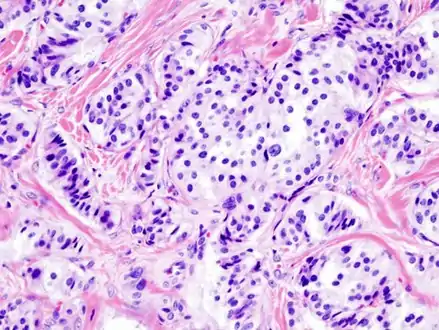

Pathology of pancreatic endocrine tumour (insulinoma). | |

- Pancreatic insulinoma